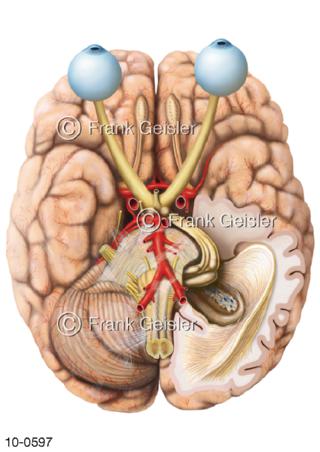

Bildergalerie Nervensystem

Bilder zum Nervensystem,dem Gehirn, Teil des zentralen Nervensystem, Zentralnervensystem ZNSmit Rückenmark, Abbildungen zum Nervengeflecht (Nervenplexus), die Verflechtungen von Nervenfasern, aus der Wirbelsäule hervortretende Nervenäst sowie Nervenzellen der Nerven